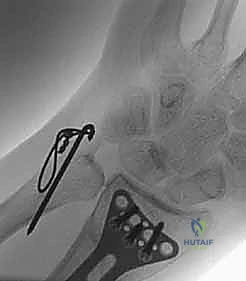

1. الأشعة السينية (X-rays): بوضعيات متعددة (أمامية خلفية، وجانبية دقيقة). الوضعية الجانبية الحقيقية (True Lateral) حاسمة لاكتشاف أي خلع جزئي في المفصل (DRUJ).

2. الأشعة المقطعية ثلاثية الأبعاد (3D CT Scan): تُستخدم في الكسور المفتتة أو كسور رأس الزند المفصلية المعقدة، حيث تعطي خريطة دقيقة للجراح قبل الدخول لغرفة العمليات.

ثانياً: العلاج الجراحي (Surgical Intervention)

خطوات التدخل الجراحي الدقيق مع الأستاذ الدكتور محمد هطيف

تُعد جراحات المعصم والزند من الجراحات الدقيقة التي تتطلب مهارة عالية، وهو المجال الذي يتفوق فيه الأستاذ الدكتور محمد هطيف بفضل استخدامه لتقنيات الجراحة المجهرية (Microsurgery) والأدوات الجراحية ذات التقنية العالية.

يقوم الدكتور هطيف بدراسة الأشعة المقطعية ثلاثية الأبعاد بدقة، ويختار نوع وحجم الصفائح المعدنية (Plates) والمسامير (Screws) المناسبة لكل مريض بناءً على حجم العظم ونوع الكسر.